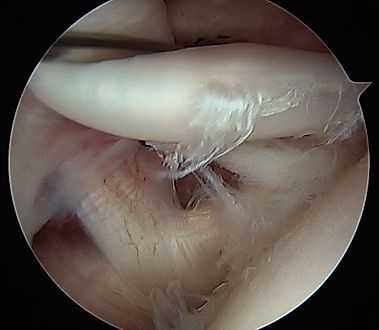

Arthroscopic imaging of tearing along the intra-articular portion of the biceps long head tendon.

Arthroscopic imaging of tearing along the superior labrum, also termed a "SLAP" tear.